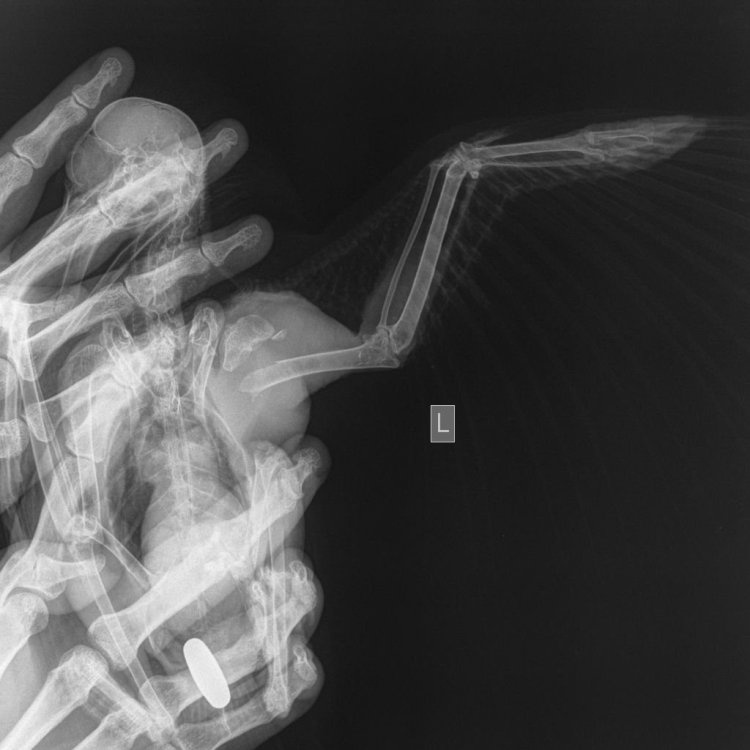

Добрый день, друзья. Вчера подобрали грачика со сломанным крылом. Сделали сразу рентген, правда в одной проекции, но ладно хоть нашли кто вообще согласился рентгенить птицу. Во многих клиниках отказ. Чувствует себя хорошо, помет жёлтый иногда белый и чуть с зеленцой. Ест творог, яйца, перловку, гречу, рис, полюбился ему виноград, также ел рябину, клюкву, семечки, орехи. Но вот мясо не ест. Совсем, ни вареное ни сырое. Тощий, киль торчит, но оперение шикарное. Крыло сломано в плечк, висит. Подрезали оперение. Прыгает, сидит на присаде. Спокойный, не кусается (в отличии от вороны). Вопросов много. У нас ещё живёт голубь. Есть ли опасность чем нибудь от грача ему заразиться? Нужны ли какие антибиотики грачу? Плечо опухшее, словно нарост, ран нет совсем, все сухо и чисто. Как быть с крылом? Подвязывать не получается, сам не подтягивает его. Оно ему мешает и задевает за все. Нужно ли в будущем ампутировать? Или как приучить к подвязывания. Грач спокойный очень, на удивление. Даёт гладить и чесать. Купался спокойно. Чуть чуть прикусывает, но больше из любопытства. Сейчас взвешу его. Модераторов просьба перенаправить тему в нужный раздел, если не правильно разместила.